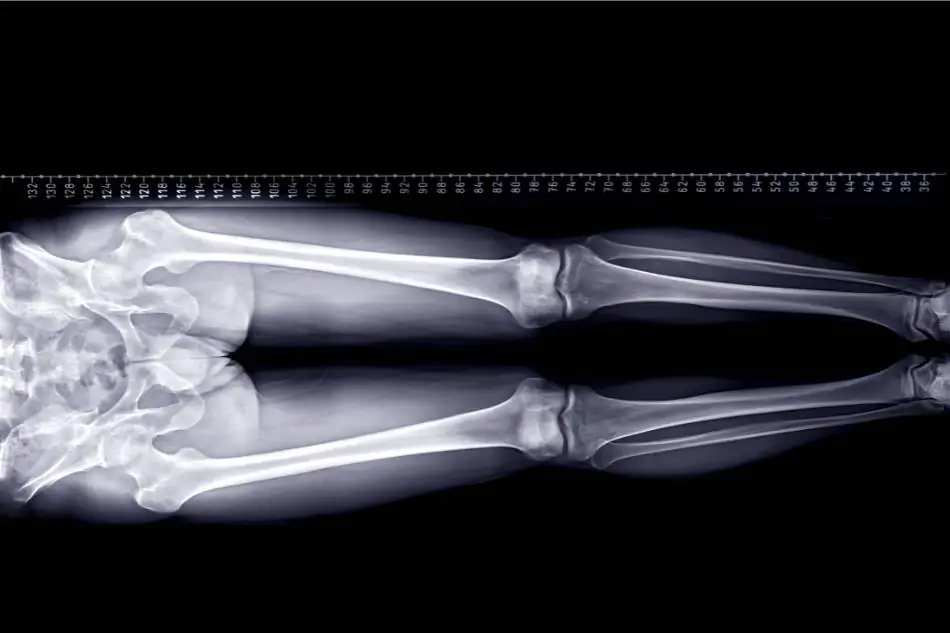

La radiografia degli arti inferiori in toto è un esame radiologico eseguito in ortostatismo, ovvero in stazione eretta, che permette di valutare le asimmetrie del bacino e degli arti inferiori.

Questo studio radiografico consente di ottenere in un’unica immagine (radiografia) una visione d’insieme che si estende dal bacino alle caviglie ed è effettuato sotto carico (in stazione eretta) in posizione frontale (AP= Antero-Posteriore).

È un’indagine utile a rilevare eventuali asimmetrie degli arti inferiori, nonché la presenza di valgismo o varismo del ginocchio. Queste problematiche possono provocare dolore dovuto a comportamenti posturali errati. E’ quindi importante individuare precocemente il problema per porre in atto azioni correttive.

Le immagini verranno poi valutate anche tramite l’ausilio di una griglia che consente di confrontare le simmetrie/asimmetrie ossee (per esempio delle creste iliache o delle caviglie)